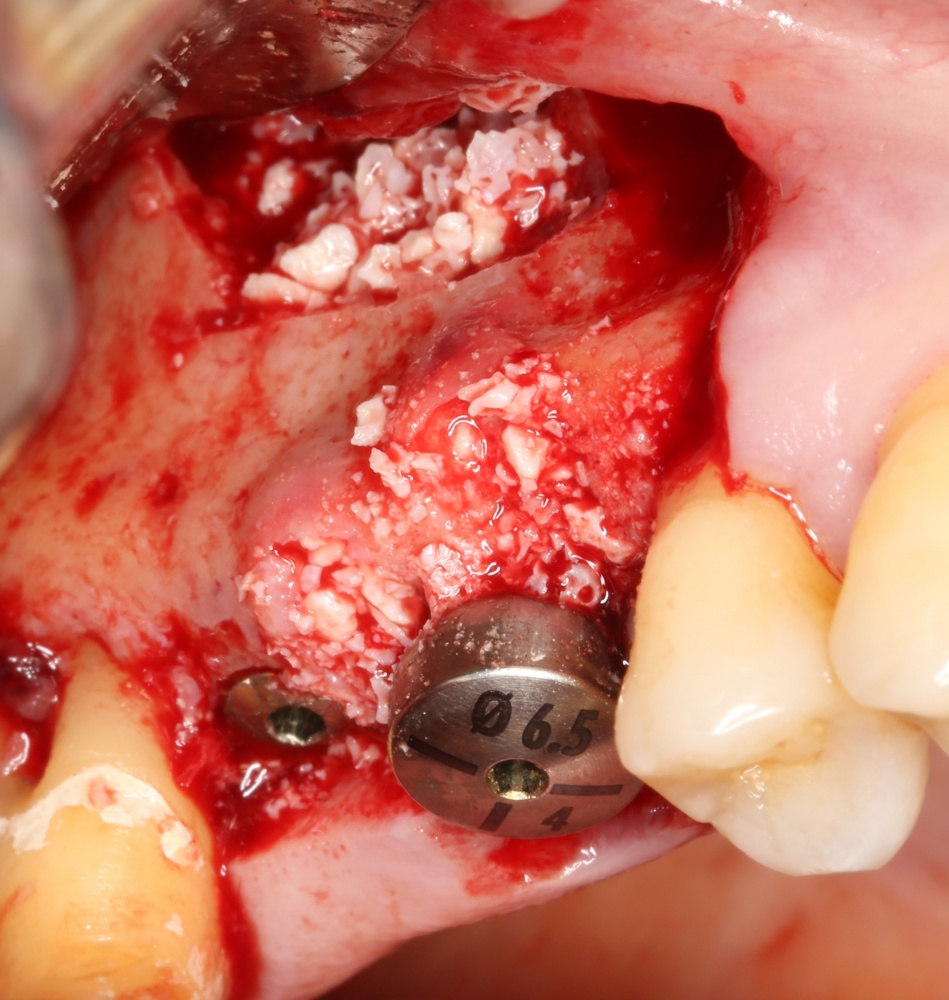

Установка имплантатов.

Напомню, что для этой работы я выбрал субкрестальные имплантаты Ankylos C/X. Они прекрасно сочетаются с любым методом остеопластики.

Я не планирую установку супраструктур или коронок, поэтому на уровень первичной стабильности можно положить болт. Даже наоборот — чем меньше крутящий момент при установке, тем лучше. Для имплантатов Ankylos и подобных им, это особенно важно. В общем, момент силы при установке — не более 10-15 Нсм.

Ремарка: имплантаты с предустановленными имплантодержателями хороши тем, что с ними легко контролировать позиционирование имплантатов. В случае с Ankylos С/Х - еще и крутящий момент. Имплантодержатель должен отсоединяться от имплантата с легким щелчком. Если его клинит, и тебе приходится прикладывать для этого усилия, то ты, однозначно, превысил момент силы во время установки имплантата. Следовательно, жди проблем.

Глянем на то, что получилось: